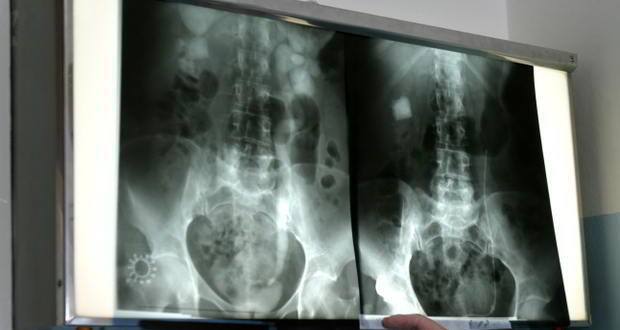

Kidney-xrayKidney stones afflict millions of people worldwide every year, triggering a crippling pain that is among the worst known to man.

Most kidney stones form when the urine becomes too concentrated, allowing minerals like calcium to crystallize and stick together. Diet plays a role in the condition -- not drinking enough water or eating too much salt (which binds to calcium) also increases the risk of stones.

But genes are partly to blame. A common genetic variation in a gene called claudin-14 recently has been linked to a substantial increase in risk -- roughly 65 percent -- of getting kidney stones.